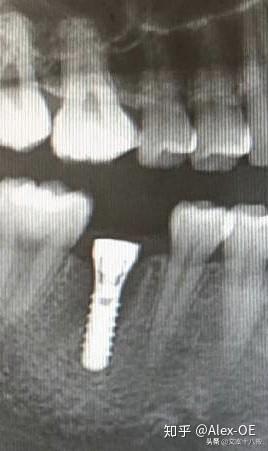

2018年7月6日,下午先拍了CT,很小劑量的輻射。主任方醫(yī)師說我的情況符合植牙條件,骨量也沒有問題,接下來安排了方案并開始手術(shù),由方醫(yī)師操刀,整個(gè)手術(shù)由3個(gè)醫(yī)生共同完成。用消毒水漱口兩分鐘后,躺在那個(gè)椅子上,燈光刺眼,消毒棉花在口腔周圍一圈一圈得涂,鼻子上都涂了。身上蓋了做手術(shù)的綠布(這個(gè)布有名稱嗎?),只露出口腔。因?yàn)檠劬σ苍诰G布底下,所以手術(shù)全程看不到醫(yī)生用過哪些工具,只能想象醫(yī)生在干什么,做了麻醉感覺不到切開牙齦,鉆孔的疼痛,但是植入牙體是有感覺的,畢竟那么大的東西硬生生的塞了進(jìn)去,從醫(yī)生手肘的顫動(dòng)知道這牙題塞進(jìn)牙槽骨挺費(fèi)勁的。術(shù)前忘記看時(shí)間了,估計(jì)今天整個(gè)過程開始到結(jié)束大概40分鐘,40分鐘內(nèi)還包括了十幾分鐘的醫(yī)生的清潔準(zhǔn)備工作。沒有什么不適,不過醫(yī)生有一會(huì)兒手碰巧壓住鼻子上面的綠布了,就只能用嘴呼吸了。我也沒提醒醫(yī)生覺得很快就過去了,醫(yī)生說有任何不適可以隨時(shí)叫停。(因?yàn)樵谇鍧嵉木G布底下,隨意抬手示意會(huì)造成污染,能不停就別停了,真的有不適吱聲就行)沒告訴他,大概憋了快一分鐘氣覺得種牙還沒有拔牙痛,只是長(zhǎng)時(shí)間張著嘴比較難受,術(shù)后拍片醫(yī)生說果不錯(cuò),配了消炎藥和漱口水,臉貼著冰袋回去了,一周后拆線?,F(xiàn)在已經(jīng)過去8個(gè)小時(shí)了,麻醉藥也過了,有少量滲血,但疼痛感十分輕微。植牙回去以后,怕麻醉藥過去后疼,下午2點(diǎn)植入后敷冰袋到了晚上8點(diǎn)。那時(shí)候確實(shí)感覺到疼,不過是輕微而持續(xù)的疼,并且這種輕微的疼大概持續(xù)了四天,術(shù)后配的藥也差不多吃完,那之后就沒事了。

2018年8月15日,距離植入牙根一個(gè)多月過去了,現(xiàn)在可以舔到那個(gè)缺牙的中間有個(gè)硬東西。它像個(gè)螺釘,上面有個(gè)釘帽,打開這個(gè)帽子是內(nèi)螺紋,到時(shí)候用來固定牙冠的?,F(xiàn)在是漫長(zhǎng)的等待時(shí)間,等人造牙根和我的牙槽骨長(zhǎng)在一起,醫(yī)生說大概3-5個(gè)月后去做牙冠。現(xiàn)階段要注意牙齒的清潔(哪時(shí)候都要,只是現(xiàn)在怕了,特別重視刷牙),從6月開始用上了菲利普的電動(dòng)牙刷,感覺不錯(cuò)的,比手動(dòng)干凈,剛開始震的不習(xí)慣,用久了發(fā)現(xiàn)很舒服。